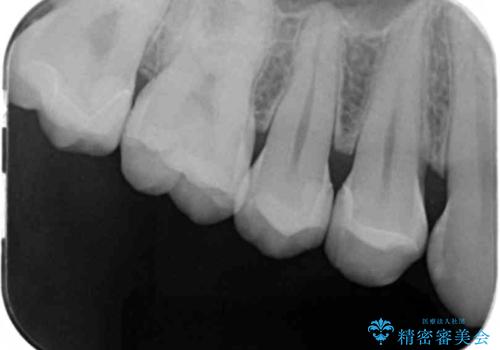

- 検査の結果左上の歯と歯の間に虫歯が発見された患者様です。

虫歯の除去後セラミックインレーでの修復処置をしていきます。